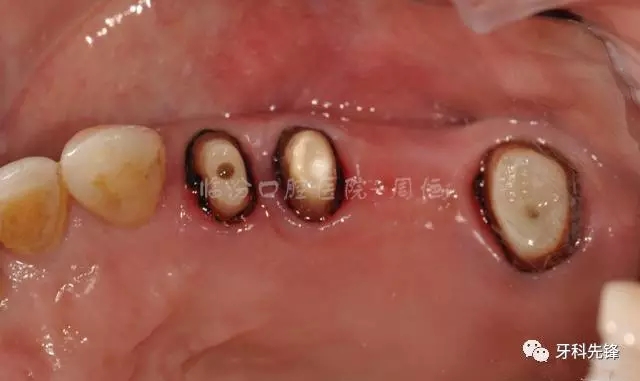

圖6拆除原修復(fù)體頜面照

640.webp (7).jpg